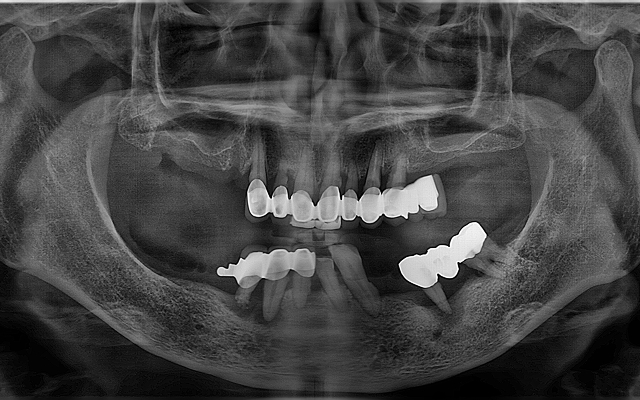

전악 케이스

- 상·하악 전체 보철 설계를 통해 정확한 교합(물림) 회복

- 심미·발음·저작 기능을 종합 고려한 자연스러운 전악 임플란트